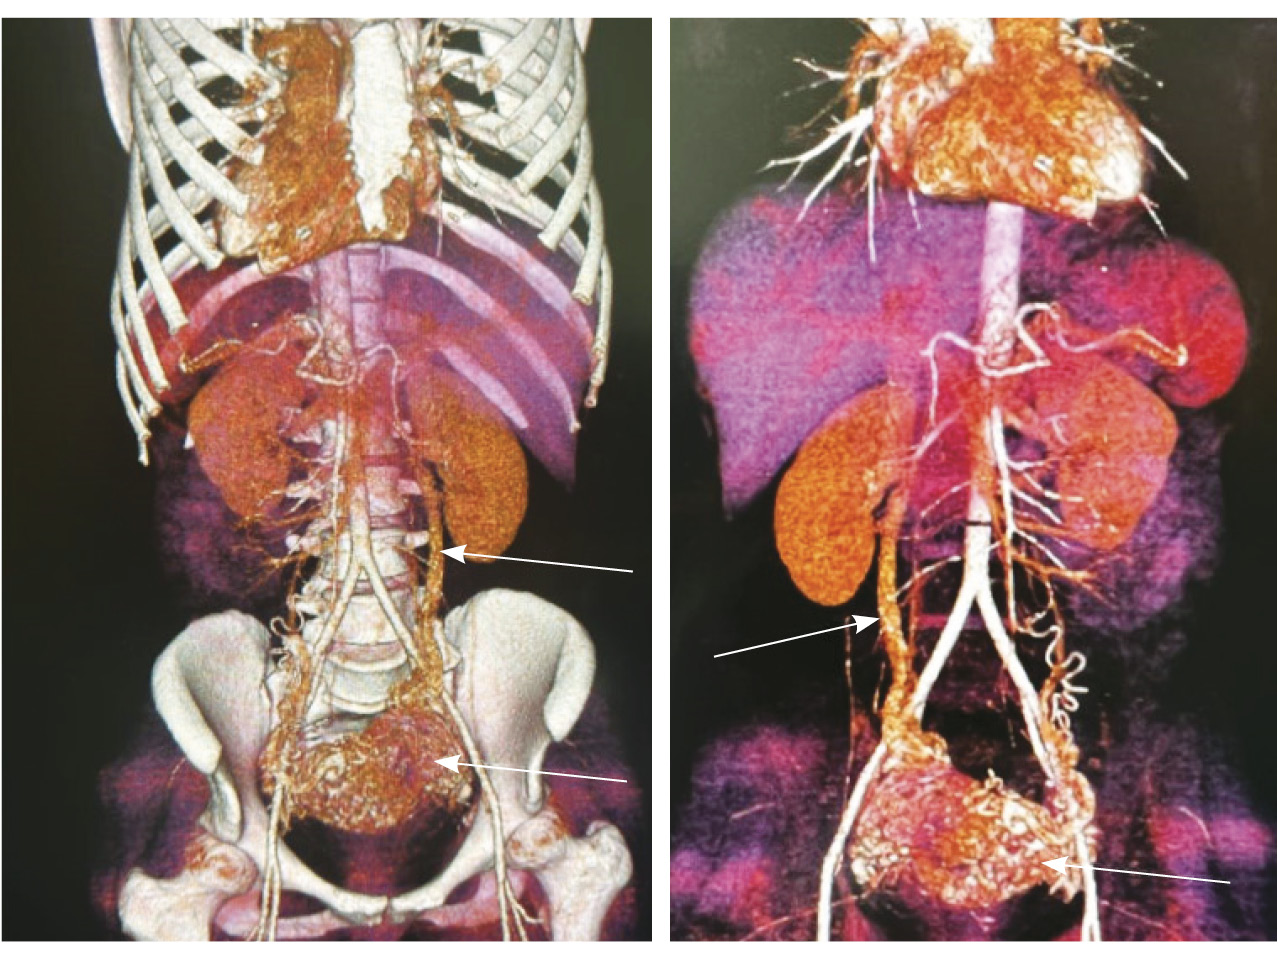

Выполнена эмболизация маточных и цервиковагинальных артерий с обеих сторон материалом PVA (1000 мкм) и эмболами из гемостатической губки. На контрольных ангиограммах патологическое сосудистое сплетение не контрастируется, артериовенозный сброс устранен (рис. 5). Катетеры и интродьюсер удалены, выполнен компрессионный гемостаз, наложена асептическая давящая повязка. Контрастный препарат йодиксанол (320 мг йода/мл) – 300 мл. Эффективная доза – 1,8 мЗв.

Рис. 5. Контрольные снимки после эмболизации маточных и цервиковагинальных артерий. Ангиограммы бассейнов правой и левой внутренних подвздошных артерий. Правая маточная и цервиковагинальная артерии, а также патологическое сосудистое сплетение в их бассейне не контрастируются, ранний артериовенозный сброс устранен. Незначительное контрастирование сегмента патологической сети по единичной мелкой ветви внутренней подвздошной артерии справа, по двум мелким ветвям внутренней подвздошной артерии слева (указано стрелками)